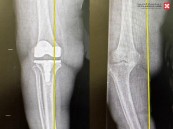

مستشفى الحبيب بالخبر يُجري عملية زراعة مفصل معقدة لإعادة قدرة المشي لثمانينية

نجح مستشفى الدكتور سليمان الحبيب بالخبر، وعبر تقنية الروبوت الجراحي "Robotic Surgery"، في إنهاء معاناة مراجعة تبلغ من العمر 84 سنة، كانت تشكو من ألم حاد ومزمن في مفصل الركبة اليسرى، أفقدها القدرة على المشي. ذكر ذلك الدكتور محمد سكيك ...